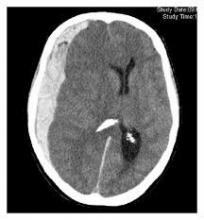

Είναι η διάταση του κοιλιακού συστήματος του εγκεφάλου, λόγω διαταραχών στην κυκλοφορία του εγκεφαλονωτιαίου υγρού του εγκεφάλου. Στους ενήλικες συνήθως...